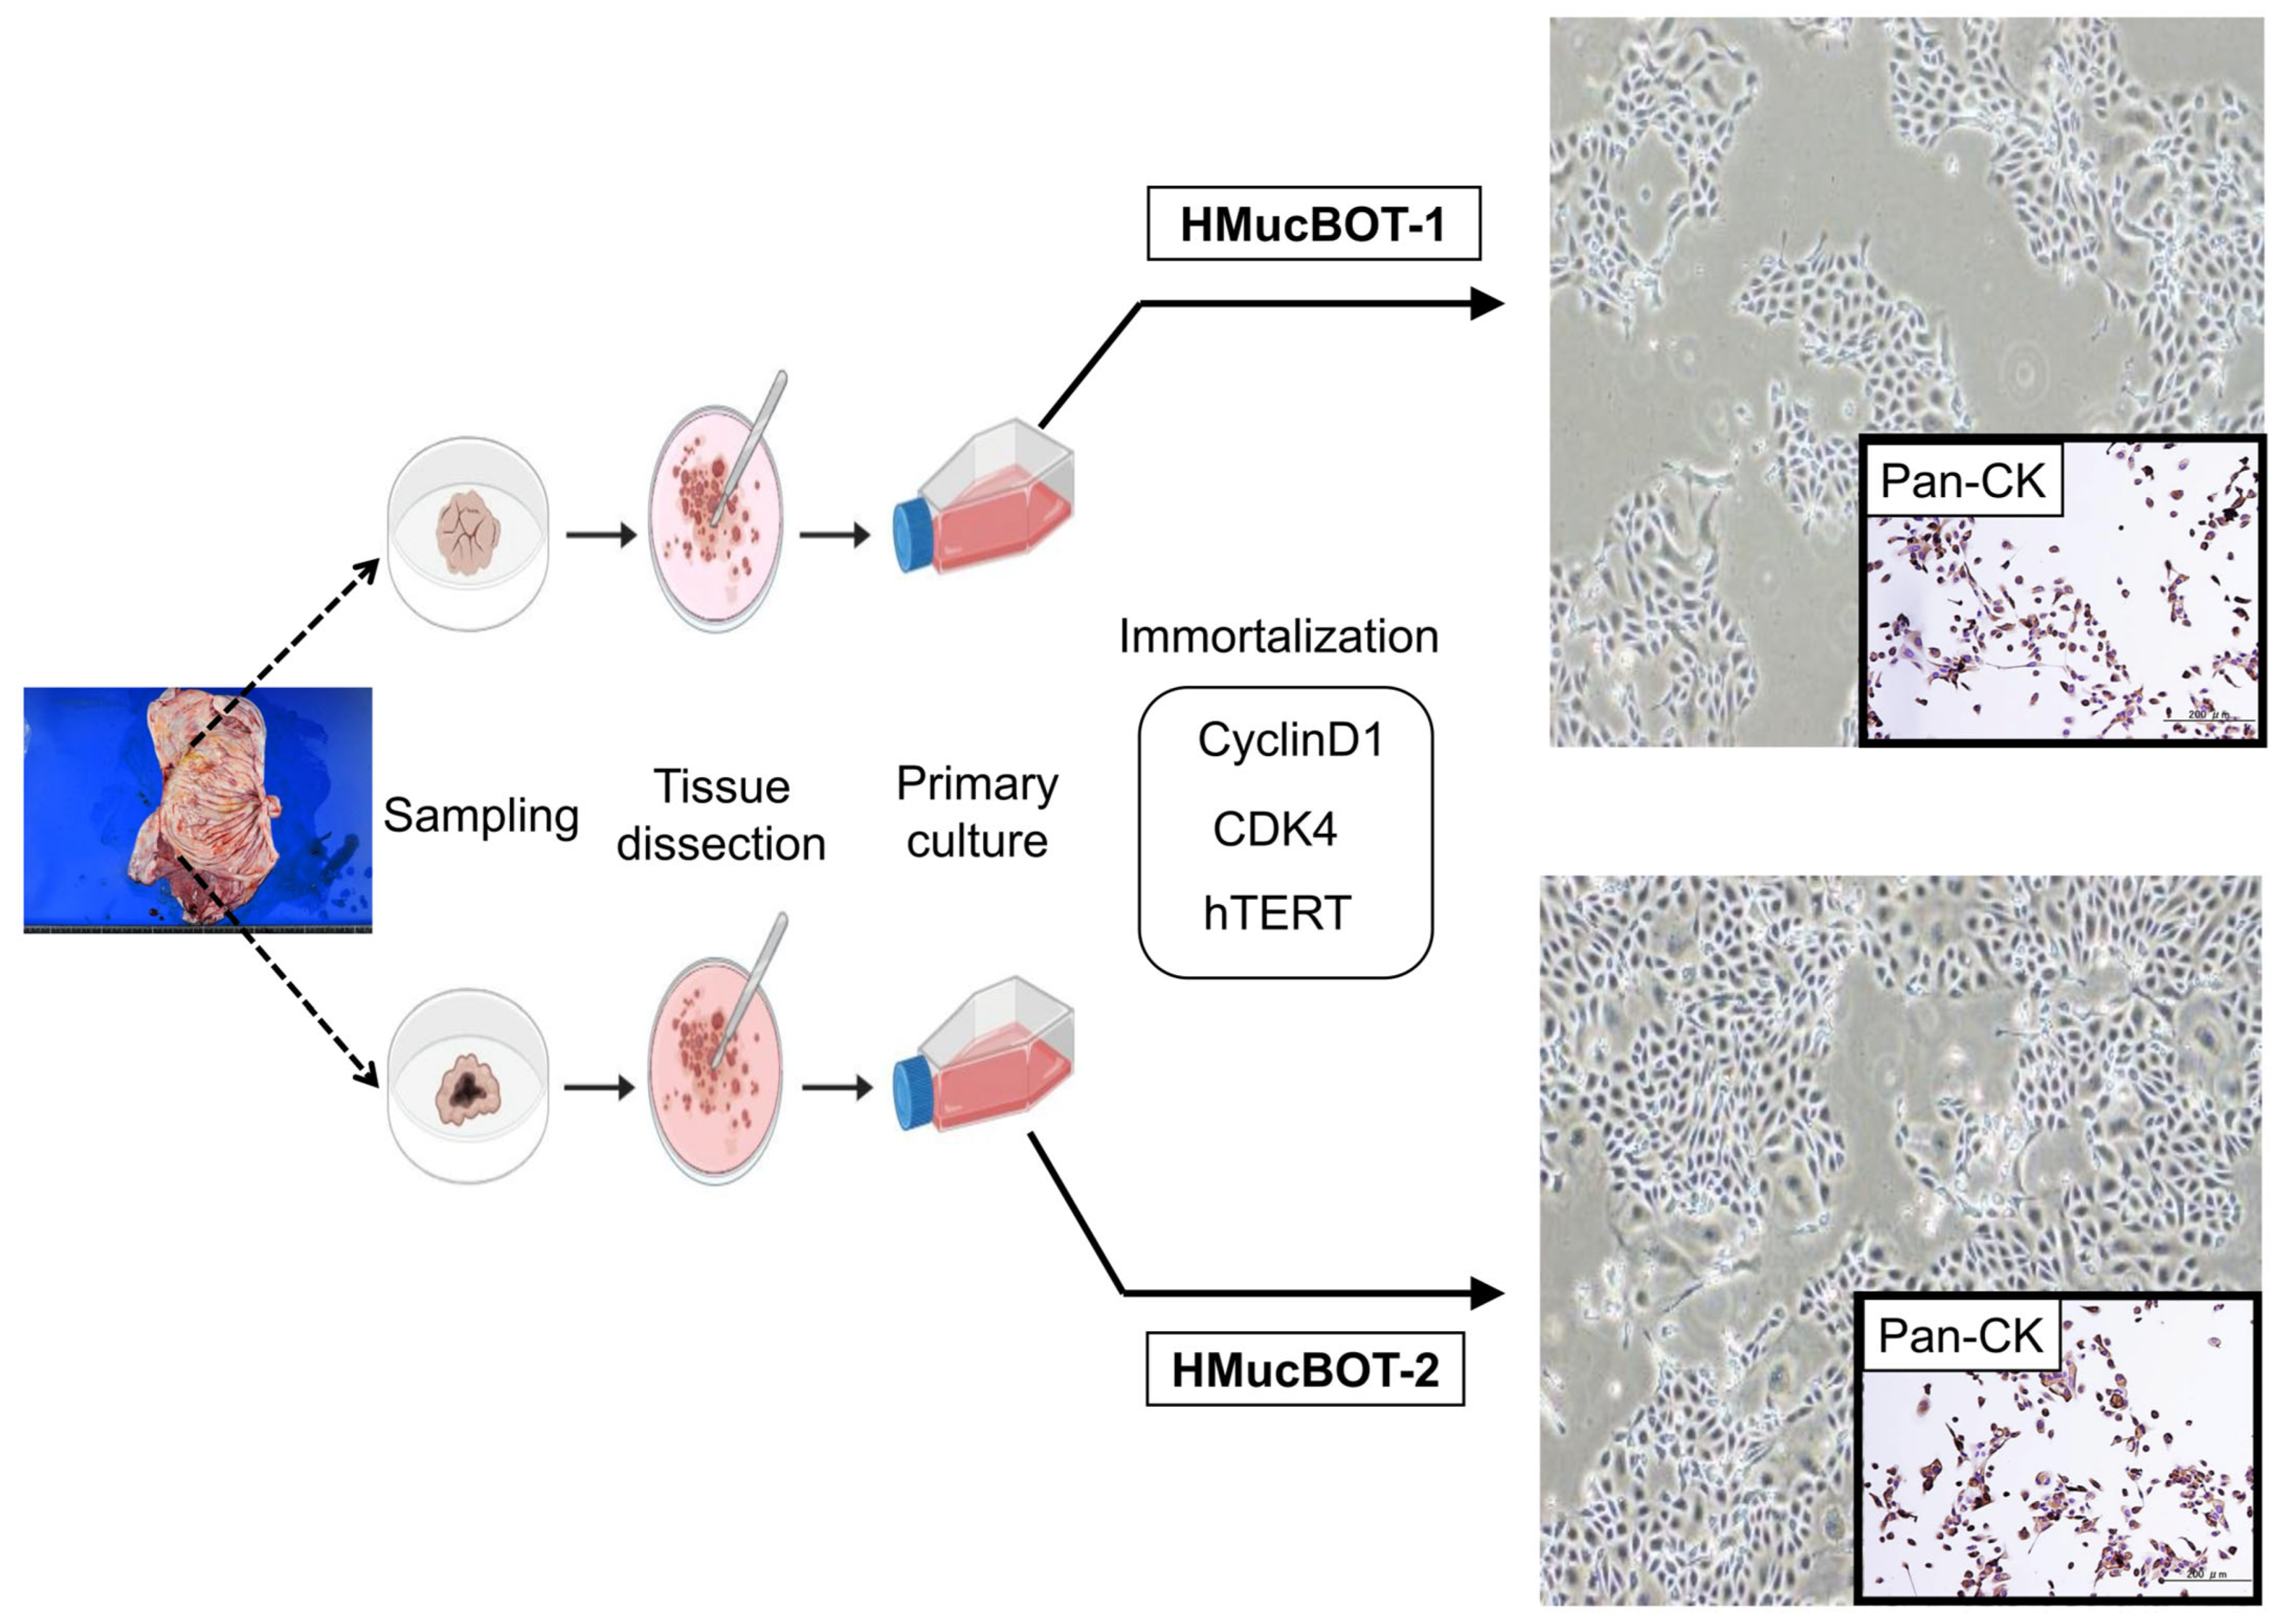

3.2. Establishment of the MBOT Cell Lines